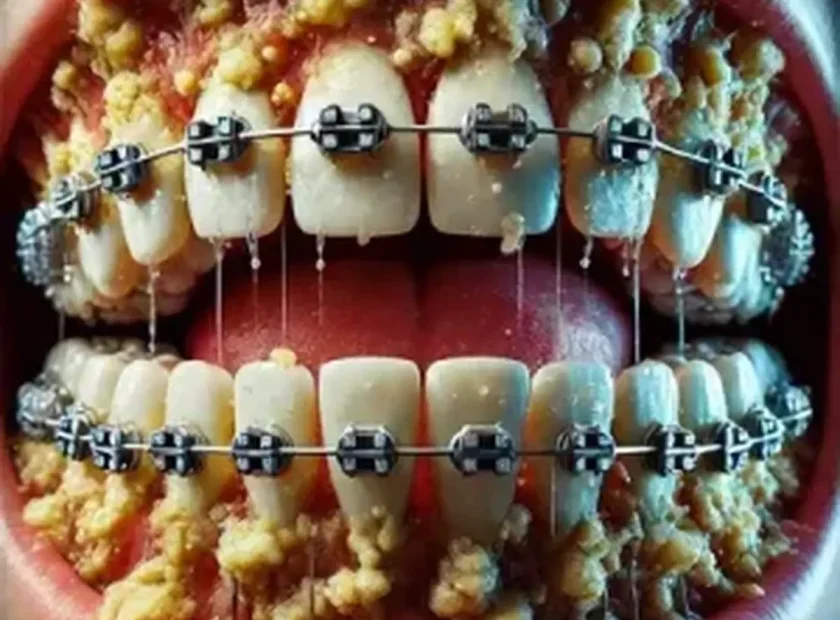

همین ترسها باعث میشود ماهها و حتی سالها جرمهای سختشدهی روی دندان، همانجا بمانند و بهتدریج زمینهساز بیماری لثه، عفونت مزمن، پوسیدگی دندان، بوی بد دهان و حتی از دست دادن دندانها شوند.

اجرای غیرحرفهای یا مراجعه به مراکز نامعتبر: استفاده از ابزار نامناسب یا فشار بیشازحد میتواند موجب خونریزی لثه، درد یا التهاب غیرعادی شود و همین تجربهی منفی باعث میشود تصور شود جرمگیری ذاتاً مضر است.

وجود بیماری لثه یا جرمهای سنگین پنهانکنندهی مشکلات: تجمع طولانیمدت پلاک باکتریایی و تارتار معمولاً مشکلاتی مانند تحلیل لثه یا لق شدن دندان را پنهان میکند. پس از حذف این جرمها، این مشکلات نمایان میشوند و بیمار تصور میکند جرمگیری باعث ایجادشان شده است.

خونریزی لثه در اثر عفونت مزمن دهان

تحلیل لثه و تخریب استخوان ناشی از جرم سخت

حساسیت دندانی و پلاک میکروبی پیشرفته

التهاب لثه شدید و تجمع سنگین تارتار دندانی